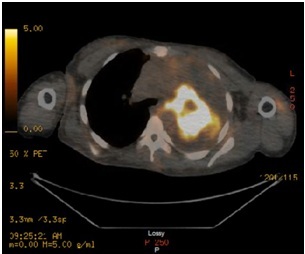

A Case of Primary Pulmonary Malignant Peripheral Nerve Sheath Tumor in a Patient with Neurofibromatosis

Ali MS, et al.

Annals of Case Reports